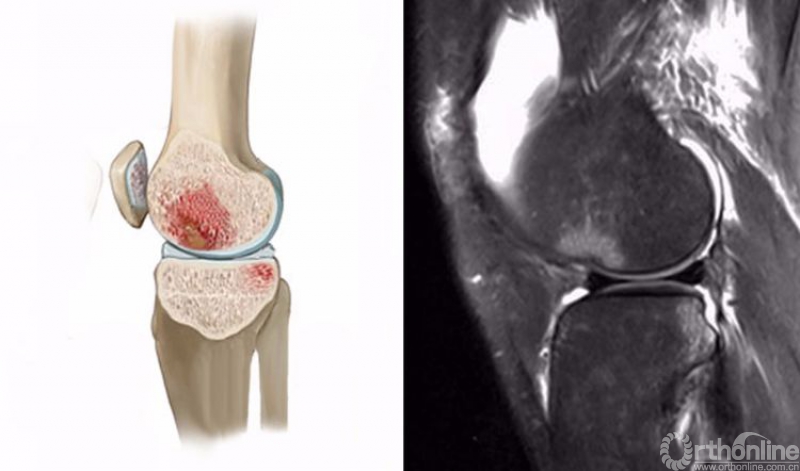

1.轴移损伤(pivot-shift injury)

膝关节在不同程度的屈曲和胫骨外旋或股骨内旋状态下,受到外翻力的作用。通常在快速减速并改变方向的时侯发生前交叉韧带(ACL)撕裂,一旦ACL撕裂,胫骨就相对于股骨前移,使股骨外侧髁和胫骨外后方撞击。其屈曲的程度决定股骨髁挫伤的部位。

膝关节轴移损伤在MRI上主要表现为股骨外侧髁和胫骨外后方骨髓水肿,T2WI及STIR像呈高信号改变,一般预示着ACL损伤。